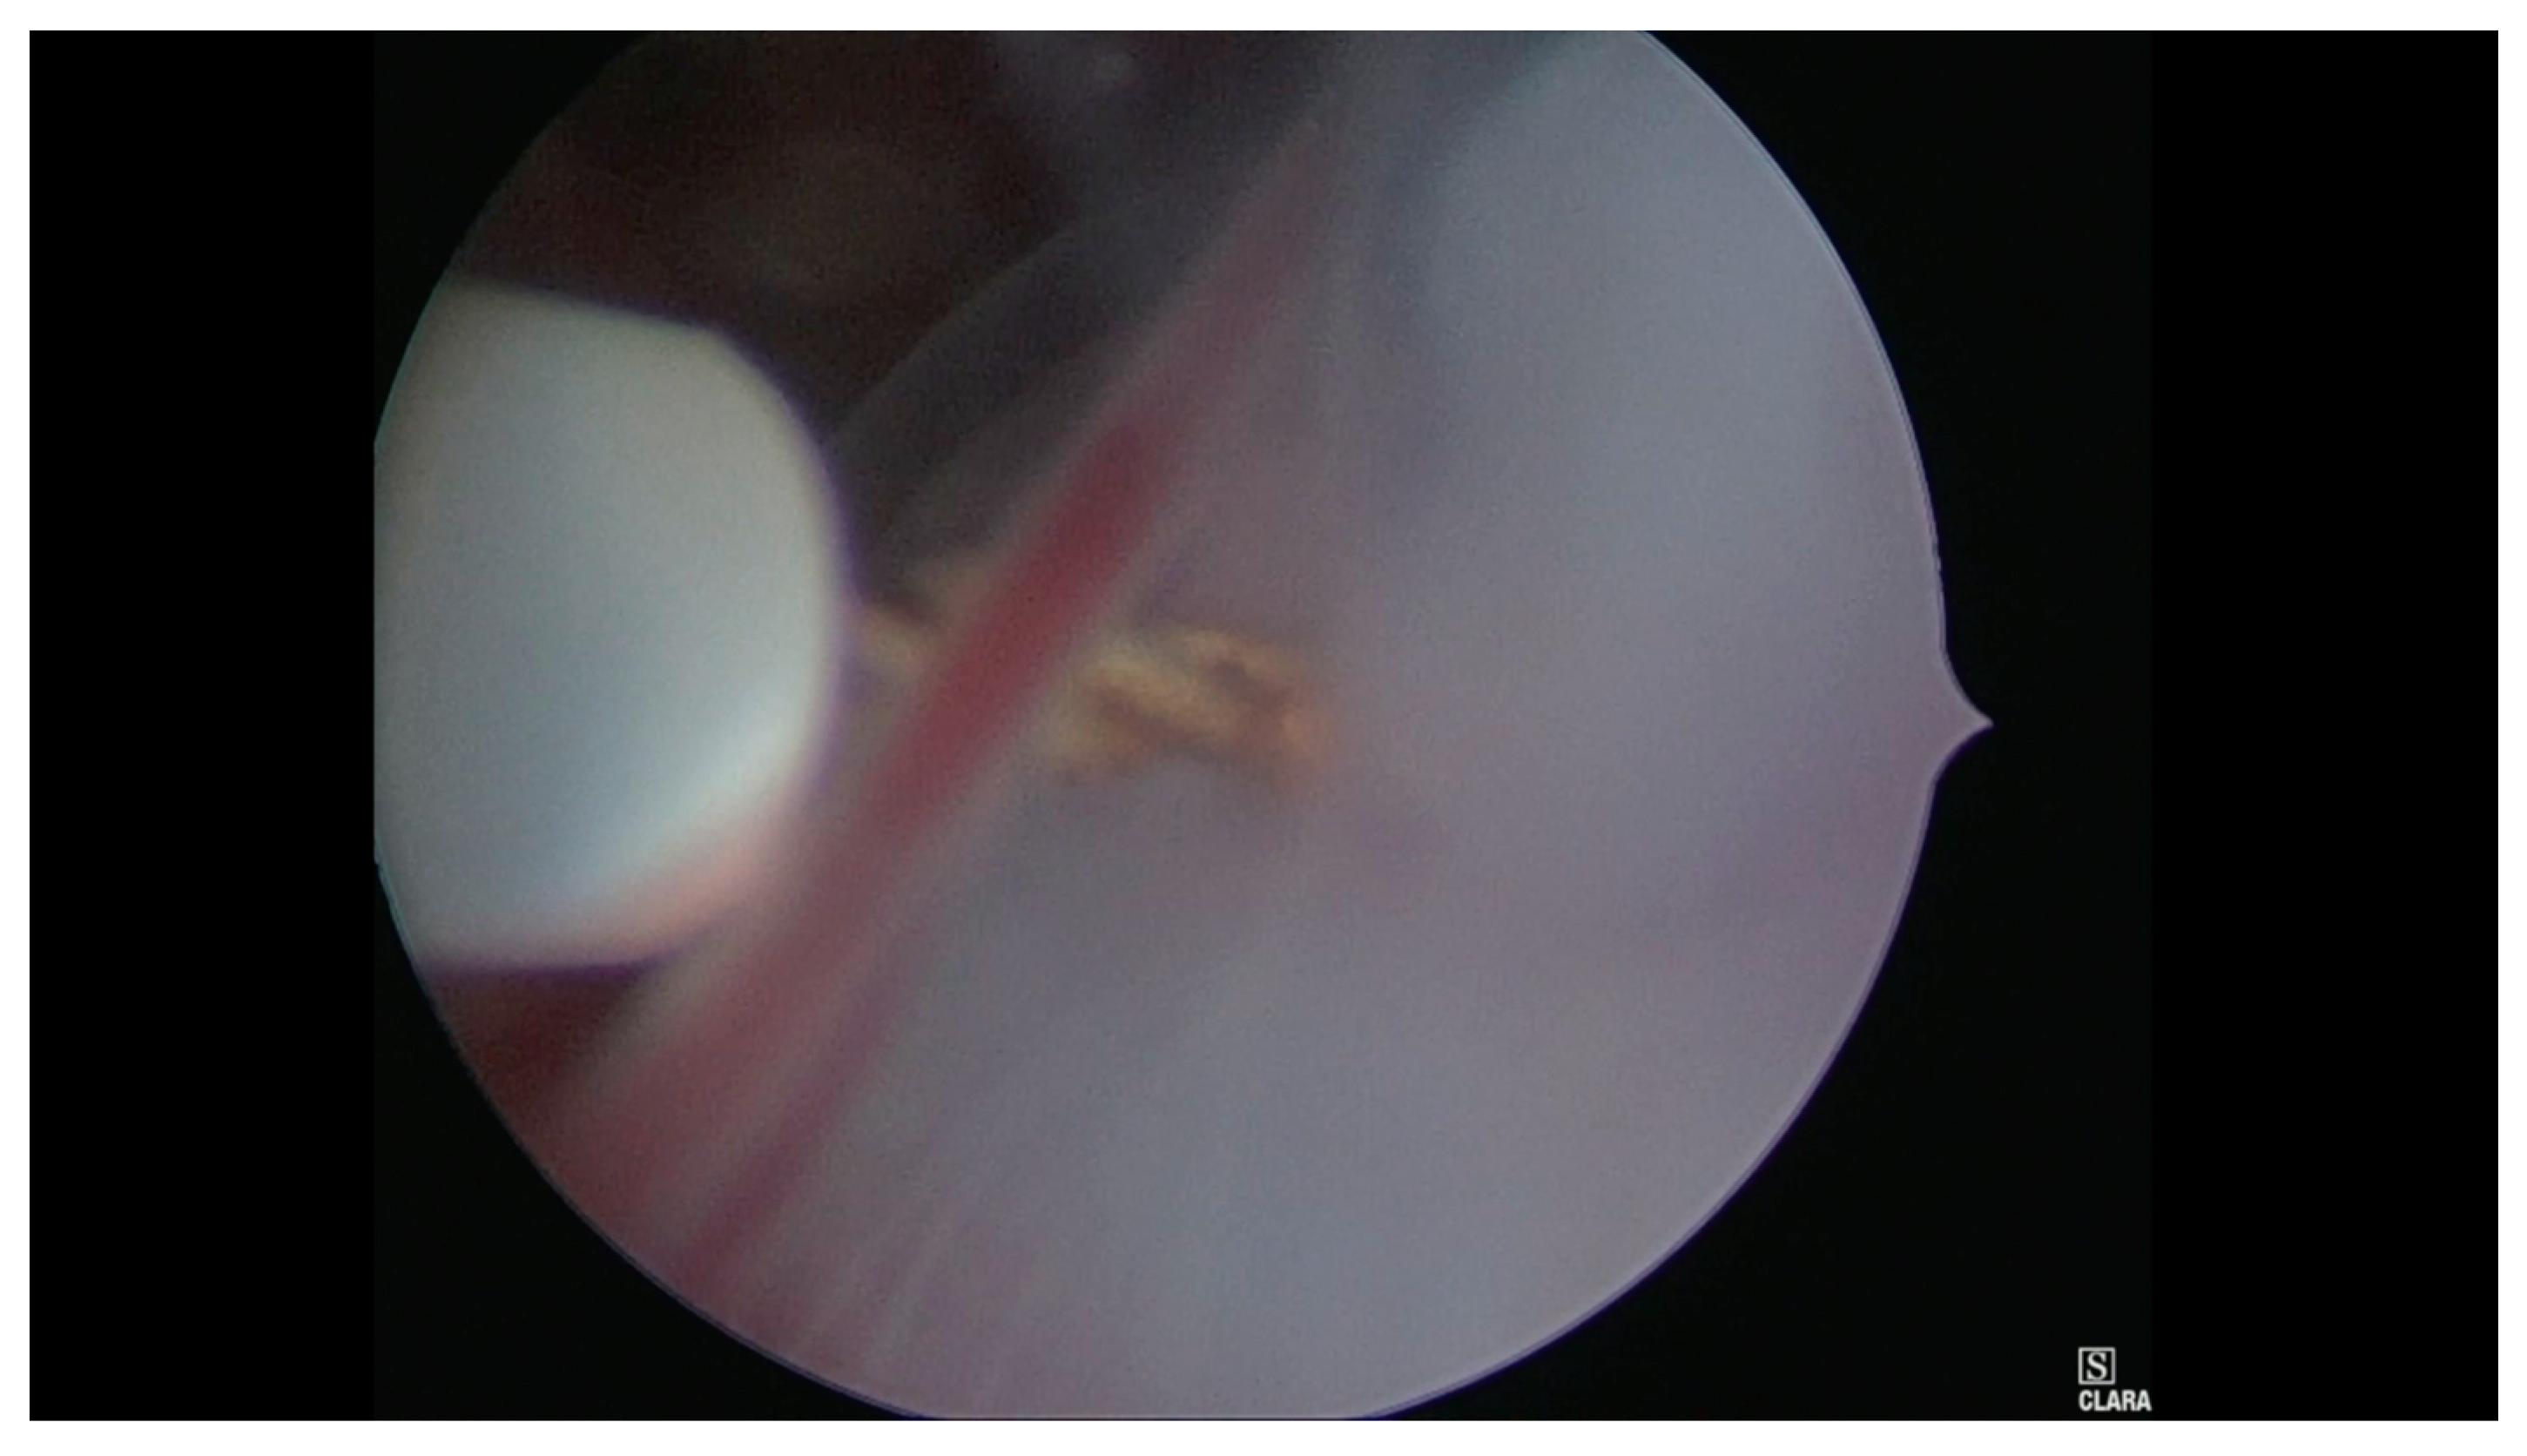

- Case 1. Hysteroscopy was performed in two steps. During the first phase a 5 mm Bettocchi hysteroscope (Storz®, Karl Storz SE & Co, Tuttlingen, Germany) with 5 Fr bipolar electrode Versapoint Twizzle (Gynecare®) was used to identify the GS: it was opened and the pregnancy terminated by cord section and vessels were partially coagulated; subsequently, the cervix was dilated and we performed a resectoscopy. During the second phase the GS and the embryo were removed and a 10 mm resectoscope with bipolar Versapoint (Gynecare®) was used to obtain a complete resection of the residual chorial villi. Lastly, we performed an electrocoagulation of the bleeding vessels on implantation site, in order to control the hemostasis (Figure 1, Figure 2, Figure 3 and Figure 4)